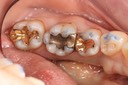

Alan Chinn #3 pre-op

Alan Chinn #3 caries removal 2

Alan Chinn #3 prep

Alan Chinn #3 finish